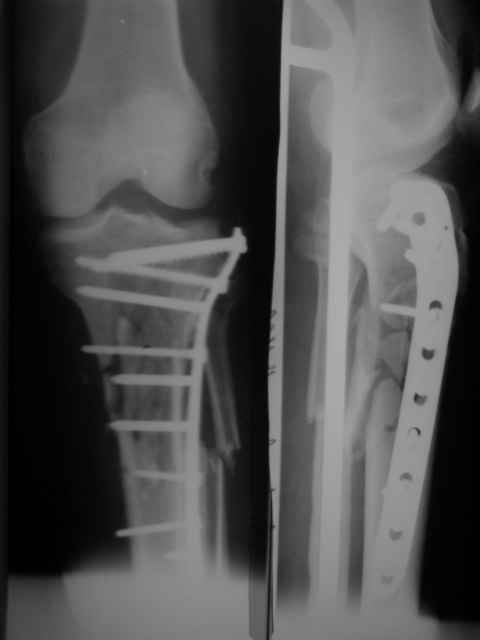

Неудовлетворительная репозиция: вальгус, диастаз по медиальному кортикалу. Наверняка репозиция была открытой недели через две после травмы, а значит травматичной со скелетированием отломков. Наличие в диафизарной части пластины 7 ответстий не означает, что во все надо вводить винты. В метаэпифиз необходимо было ввести минимум 3 блокированных винта на всю толщу спонгиозы.

-Неудовлетворительная репозиция: вальгус, диастаз по медиальному кортикалу.

Вальгуса нет(мы не предоставили осевых снимков)

В диастазе стоит единственный отломок размером 1.2 на 2.5 по медиальной поверхности,остальные отломки всев контакте!

-В метаэпифиз необходимо было ввести минимум 3 блокированных винта на всю толщу спонгиозы.

Введено два блокируемых винта длинной 70 мм.и один спонгиозный.

-Какая (открытая или закрытая) была репозиция?

Репозиция была выполнена открыто(закрыто к сожалению не получилась-большие сроки и множество отломков)

-Чья это пластина?

LCP"SYNTHES"-прокимальная латеральная для б/берцовой кости